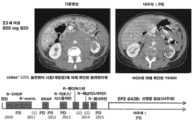

도 10은 야생형 EZH2가 사용될 때 여포성 림프종에 있어서 CR을 나타낸다.

Figure 10 shows CR in follicular lymphoma when wild-type EZH2 is used.